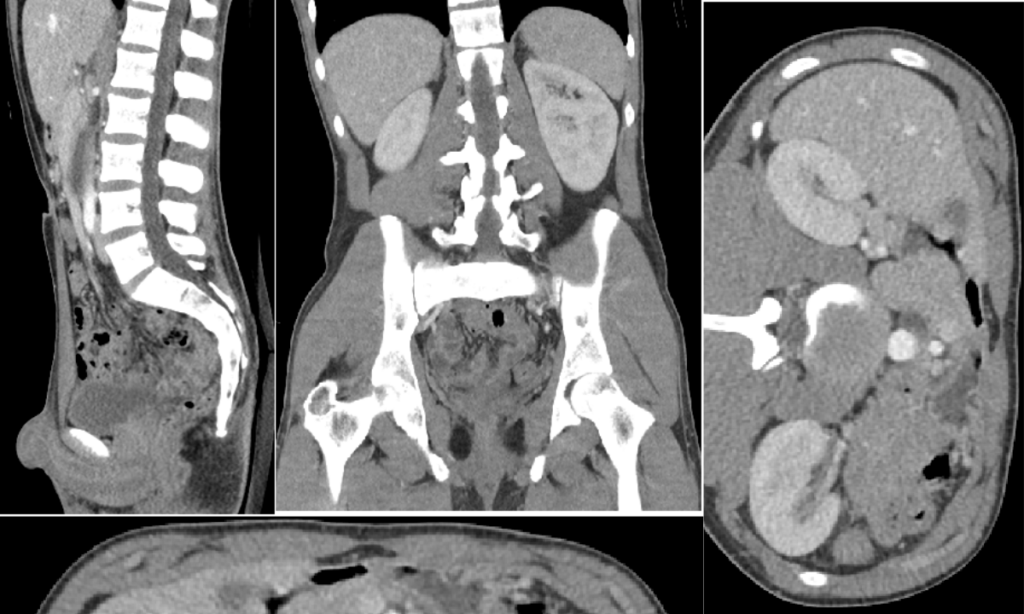

CT (Computed Tomography) Abdomen Scan एक advanced imaging test है जो पेट के अंदर के organs की cross-sectional images देता है।

यह test खासतौर पर इन स्थितियों में उपयोगी है:

- लगातार पेट दर्द

- Liver या Kidney disease

- Tumor या cancer suspicion

- Internal injury या infection

👉 Ultrasound से ज्यादा detailed और MRI से सस्ता होने के कारण CT scan बहुत common हो गया है।